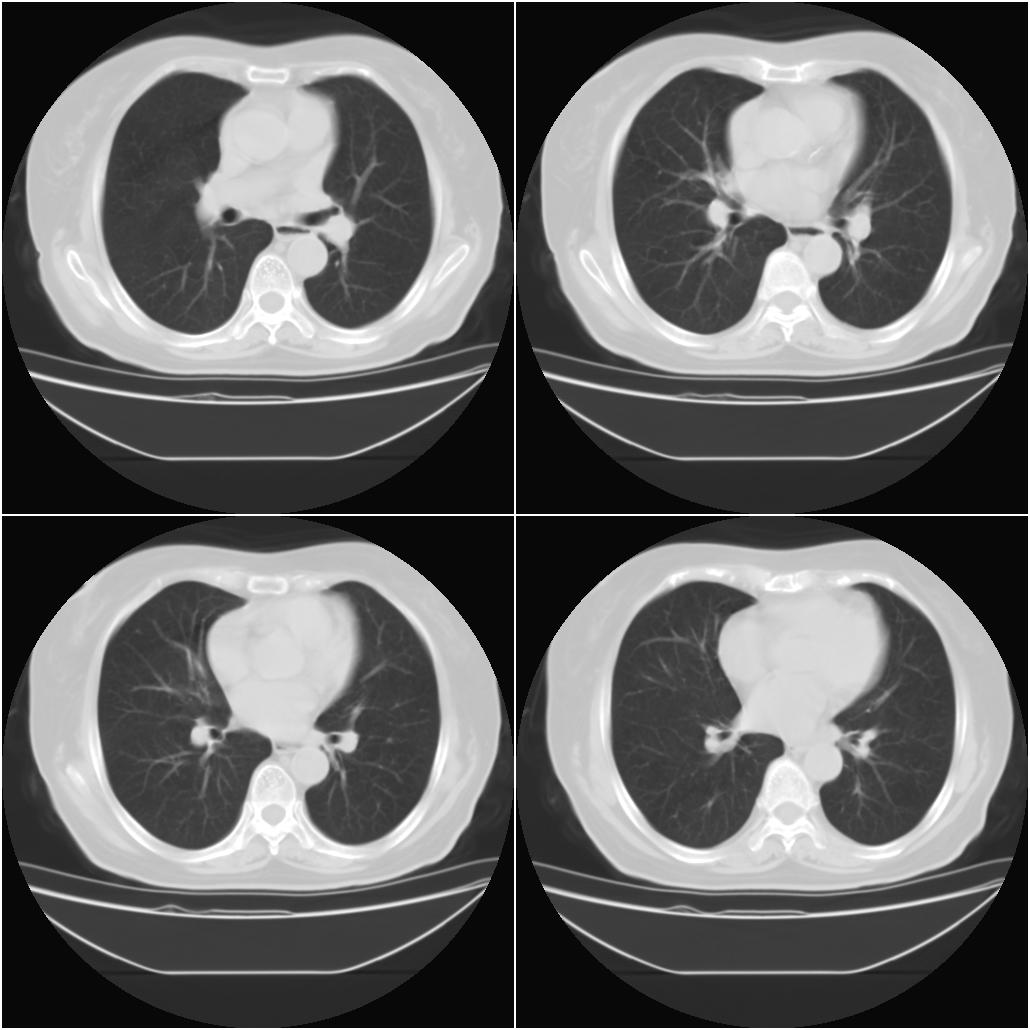

以下是引用sxlcbc在2007-12-23 4:27:00的发言:[br]气管源性肿瘤觉得有点不靠谱啊,看上去气管是受压改变的。更像是上段食管的改变,周围淋巴结肿大,食管受压。看看以下六幅图片:[br]不过,有一点不好理解:食管肿瘤应该有食道症状的,再说食管癌出现周围这么大的淋巴结也不多见啊,如果考虑淋巴瘤倒是更合理一点,这样气管,食管受压改变也许更合理一些。[br][br]